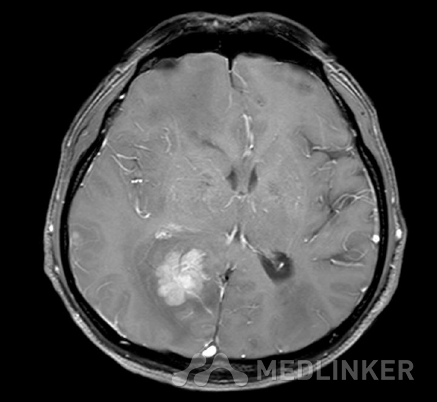

MR:1、双侧额、顶叶、右侧颞叶、枕叶、左侧颞叶岛盖皮层、皮层下区多发异常信号结节,环状或结节状强化,周围见环状、斑片状、指状水肿区,拟多发脑转移瘤。 2、双侧额顶叶皮层下区、右侧基底节、尾状核区、胼胝体区多发腔隙性缺血、部分梗塞、软化灶。 3、两侧筛窦粘膜增厚。鼻中隔稍左偏,两侧下鼻甲肥厚。

诊断:肺癌并脑转移 诊治经过:入院后完善检查,行CT检查发现脑内多发占位性病变,考虑转移瘤,遂行头颅磁共振、胸、 腹、盆腔CT增强检查,示肺部占位性病变并增强。患者及家属要求出院